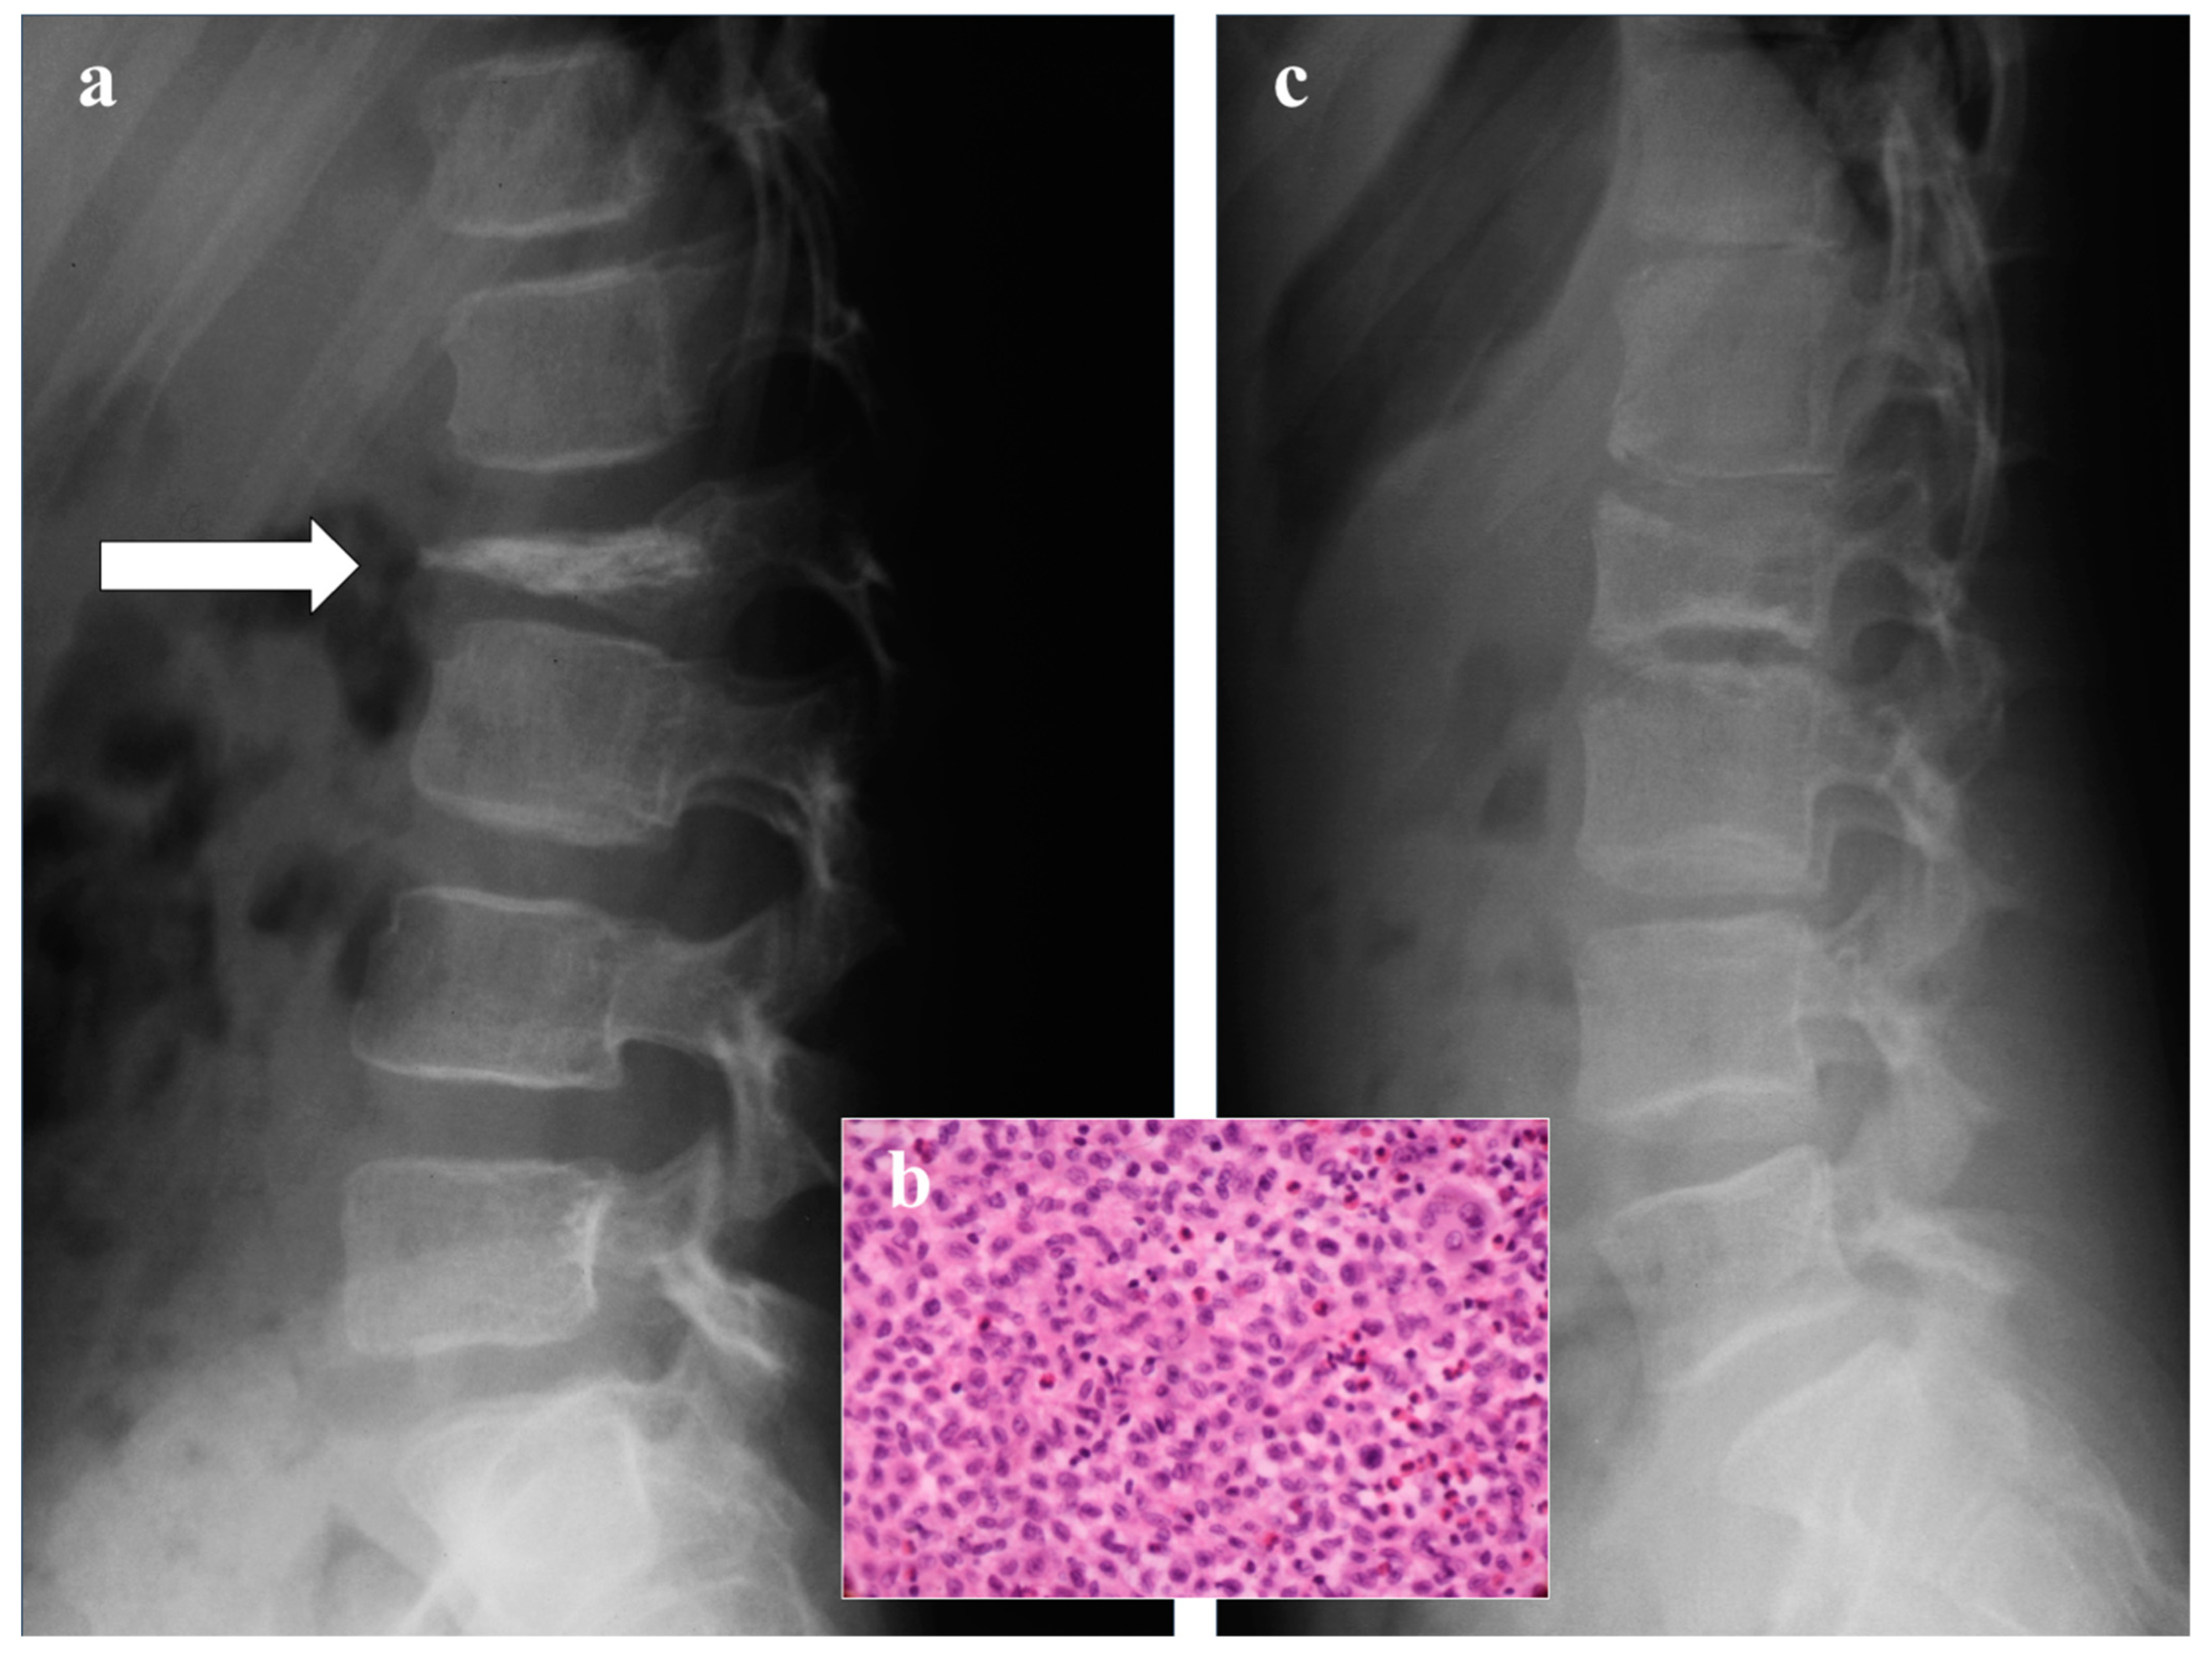

- Buhr, J. Differential diagnosis of vertebra plana: Isolated flat vertebra as an early symptom of acute leukemia. Kinderarztliche Prax. 1970, 38, 259–266. [Google Scholar]

- Solgaard, S.; Kristiansen, B. Vertebra Plana Due to a Malignant Lymphoma. Acta Orthop. 1980, 51, 267–269. [Google Scholar] [CrossRef] [PubMed]

- Zahid, M.; Ahamed, S.; Jain, J.K.; Chabra, R. Vertebra Plana with Paraplegia in a Middle-Aged Woman Caused by B-Cell Lymphoma: A Case Report. Case Rep. Orthop. 2012, 2012, 1–3. [Google Scholar] [CrossRef]

- Greenleaf, R.M.; Ricciardella, L.F.; Latona, C.R.; Sangimino, M.J. Vertebra Plana in an Adolescent Caused by Multiple Myeloma. J. Bone Jt. Surg. 2011, 93, e37. [Google Scholar] [CrossRef] [PubMed]

- Mavrogenis, A.F.; Angelini, A.; Pala, E.; Zinzani, P.; Ruggieri, P. The role of surgery for haematologic neoplasms of bone. Acta Orthop. Belg. 2012, 78, 382–392. [Google Scholar]